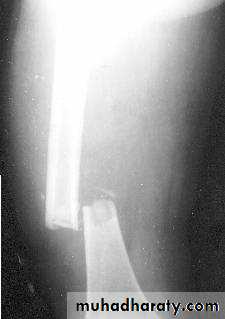

INTERNAL FIXATION

EXTERNAL FIXATIONPrinciple